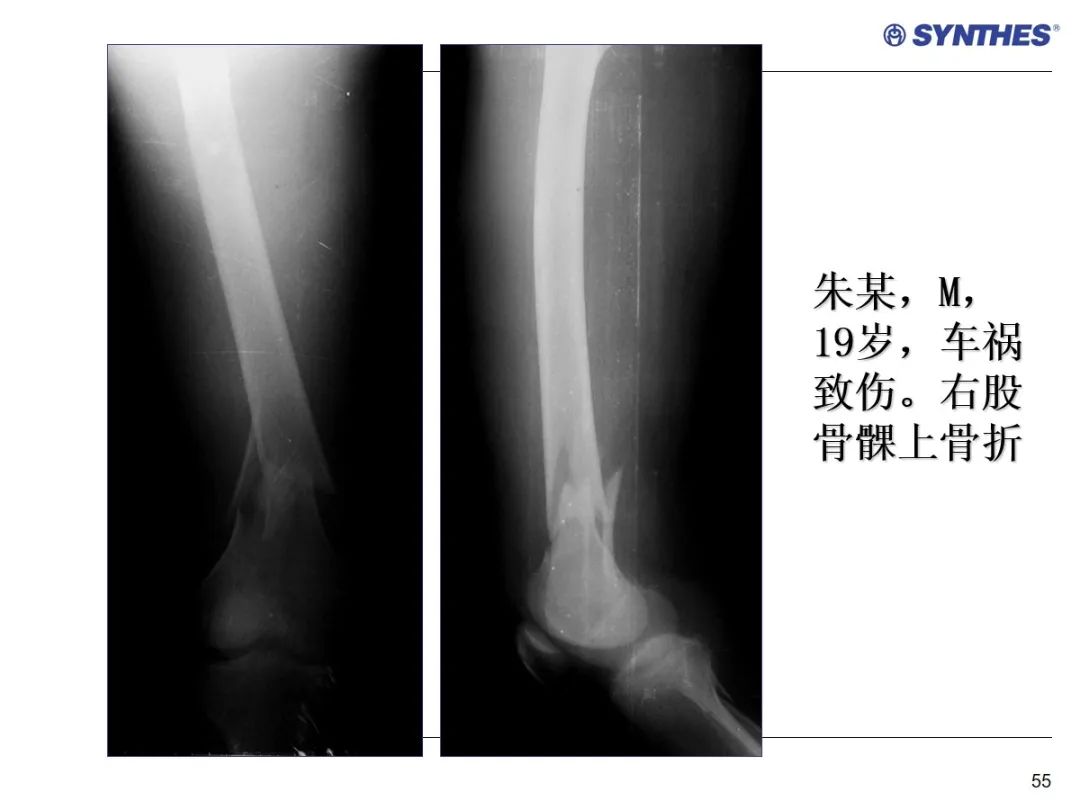

LISS微创固定系统应用技巧,原来如此简单!